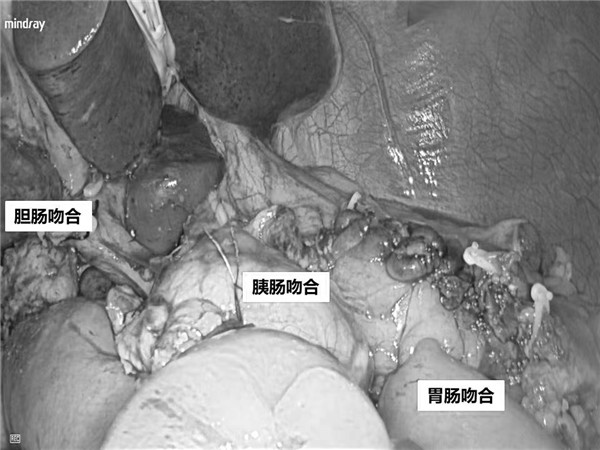

由于胆总管下段涉及十二指肠和胰腺导管开口,这个部位像西安的钟楼,一旦堵车,影响东西南北大街通行,甚至波及整个西安交通。根治性手术需要切除器官组织多,淋巴清扫范围大,消化道重建复杂,是腹部外科最具挑战性的手术之一。全腹腔镜下胰十二指肠切除术(LPD)更具有创伤小,出血少,恢复快,住院时间短,花费少等优点,但LPD需要术者在2D视野下切除胰头、胆囊、胆总管、十二指肠、部分胃和空肠,清扫区域淋巴结,完成胰肠吻合、胆肠吻合与胃肠吻合等超精细的镜下操作,难度更大,对术者的经验、技术要求更高。

经过周密的术前准备、评估和充分的医患沟通后,由普通外科陆宏伟教授主刀,卢乐主治医师和尚皓助理研究员担任助手,在麻醉手术科雷晓明主任医师、赵丽燕护士长团队的保驾护航和和精密配合下,为奥先生实施了全腹腔镜下胰十二指肠切除手术。术中情况与手术术前评估高度吻合,术中暴露良好,手术减创而不减质,在充分清扫淋巴结的同时完整保护了重要脉管,手术历时8小时,术中出血100mL。